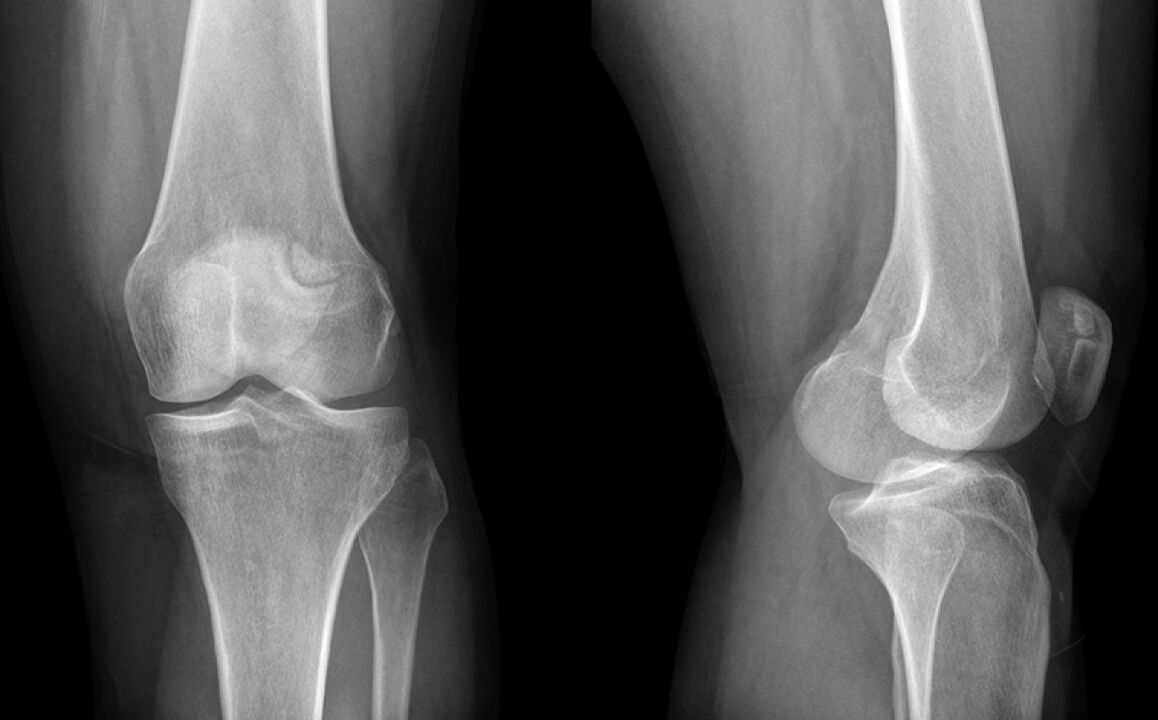

De knie deed drie weken pijn. Uiteindelijk ging ik naar een arts die de schade aan de meniscus vermoedde en naar een X -Ray werd gestuurd. De diagnose is het beginfase van artrose van het kniegewricht.